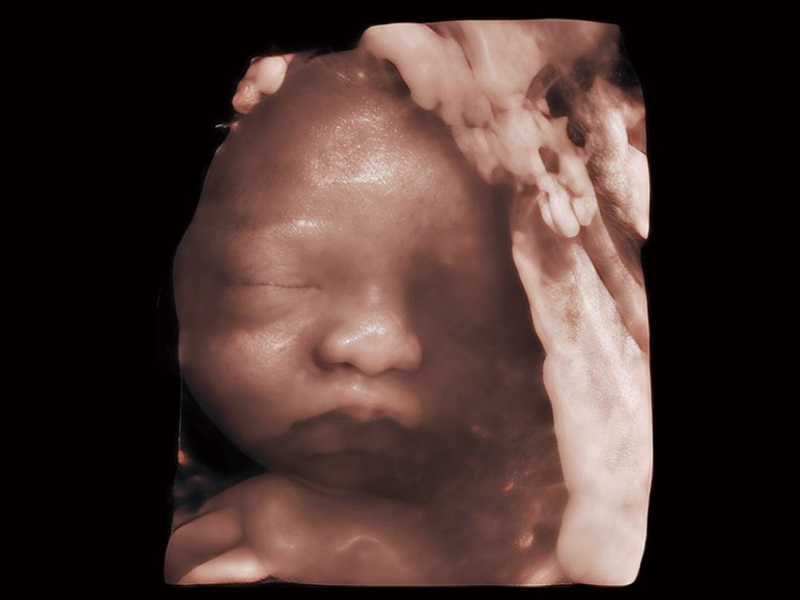

HD PORTRE

Derin öğrenme teknolojisine dayalı ,büyük veri yüz özelliklerinin uygulanması ile HD Portre , Cilt dokusu ve saç işleme yeteneklerini geliştirerek , fetal cilt görünümünü ve yüz özelliklerini ön plana çıkarır.